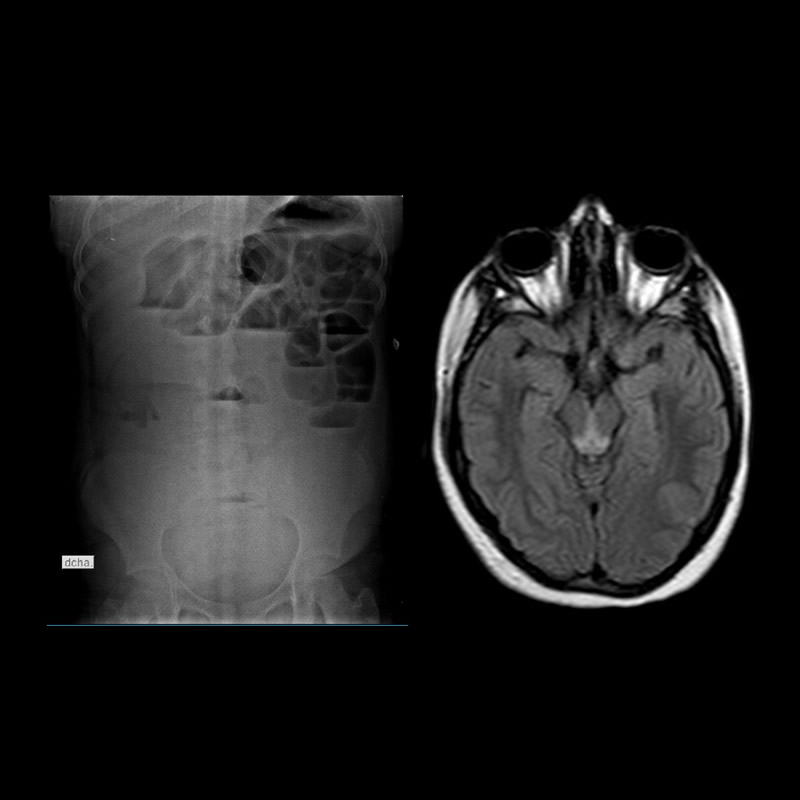

12 años – Abdomen agudo – Síndrome confusional.